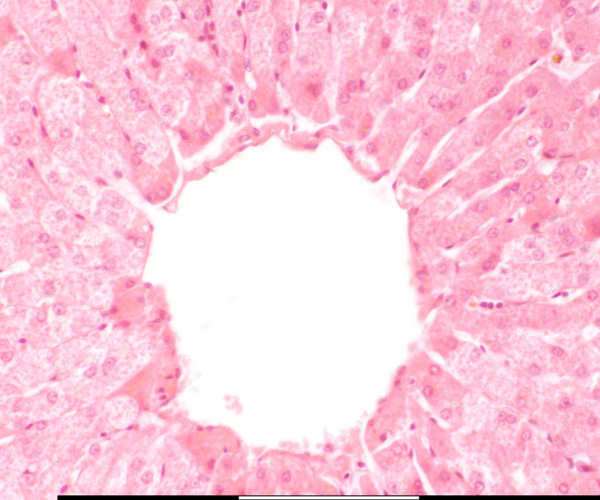

High magnification of the central vein

Sentrale vena / Central vein Bindweefsel / Connective tissue Openinge van sinusoïede / Openings of sinusoids